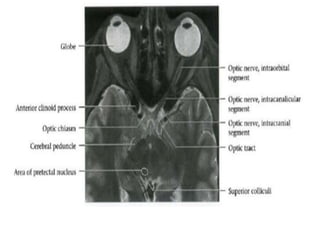

-Olfactory	bulb/tract	lies	in/below	olfactory	sulcus

-Olfactory	sulcus	defines	lateral	margin	of	gyrus	rectus.